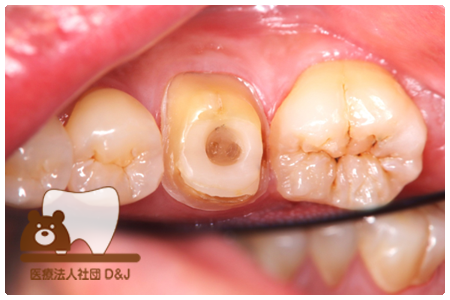

症例3フリジルコニアクラウン 左上6

治療前

治療後

59歳 男性

- 治療内容

- 虫歯で大きく失われた歯に対して、土台としてファイバーコアを使用し、その上にフルジルコニア製の被せ物を装着しました。見た目と強度を両立した自由診療の治療です。

- 治療期間

- 根の治療含めて3カ月半

- 費用

- 自費

フリジルコニアクラウン:77,000円(税込)

(R8.2月時点)

- その他の治療の費用は含まれておりません。

- リスク・副作用

- 強い力が加わると割れる可能性があります。また、噛み合わせや歯ぎしりの影響で脱離することがあります。